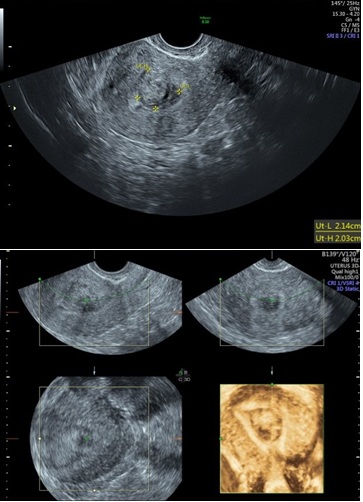

Figure 3: 2D & 3D USG showing Subseptate Uterus.

Hysteroscopy showing Submucus Fibroid in Uteruine Cavity.

Three-Dimensional Ultrasonography (3D USG) in comparison to hysteroscopy is less invasive, cheaper, easily accepted by most patients and does not require much training. In most cases an endometrial polyp can be differentiated from the submucous fibroid based on the imaging characteristics. The polyps are typically round in shape, smooth in outline, and are generally echogenic, compared to the endometrium or are isoechoic to it. The underlying endometrial-myometrial interface is preserved (Figure 5). Moreover the presence of a vascular pedicle has a positive predictive value of up to 81.3%. Fibroids are more inhomogeneous, hypoechoic, and there is a loss of endometrial-myometrial interface. The percentage of the intra cavitary portions of the submucous fibroids i.e., grade of submucous myoma can be assessed on 3D USG by the degree of distortion caused by it (Picture 6).